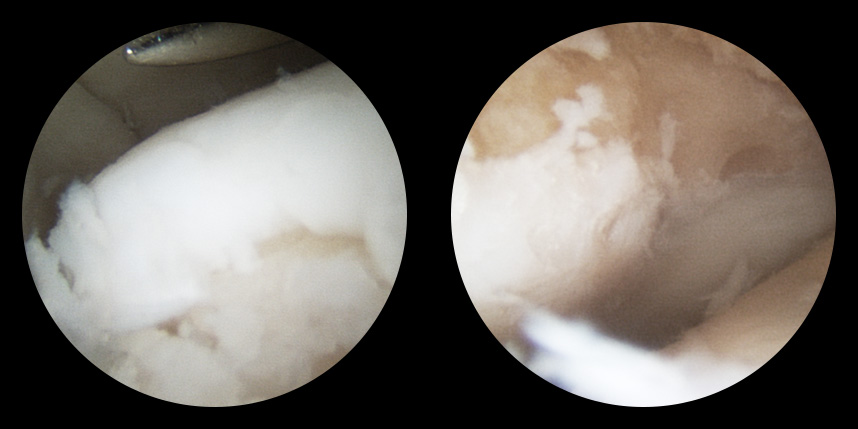

손상된 연골 부위에 작은 구멍을 뚫어 골수에서 나오는 줄기세포를 이용하여 연골 재생을 유도하는 방법으로 근본적으로 섬유연골(정상연골보다는 약한 연골)로 재생된다고 알려져 있습니다.

특수하게 농축하여 제작된 6% 콜라겐(리젠실603) 또는 9% 콜라겐(이엔카티)을 천공술을 시행한 부위에 덮어 주어 미세천공술 단독보다 좋은 치료 결과를 기대할 수 있습니다.

동종 제대혈줄기세포를 이용하여 연골 재생을 촉진하는 방법으로 초자연골에 가까운 연골로 재생되는 것을 기대할 수 있습니다.

본원에서는 미세천공술, 콜라겐주입술, 카티스템 치료를 주로 하고 있습니다.

연골 손상이 크거나 작고 어느 위치에 있어도 연골재생술이 가능합니다.

전통적으로 증명이 된 미세천공술을 항상 같이 시행